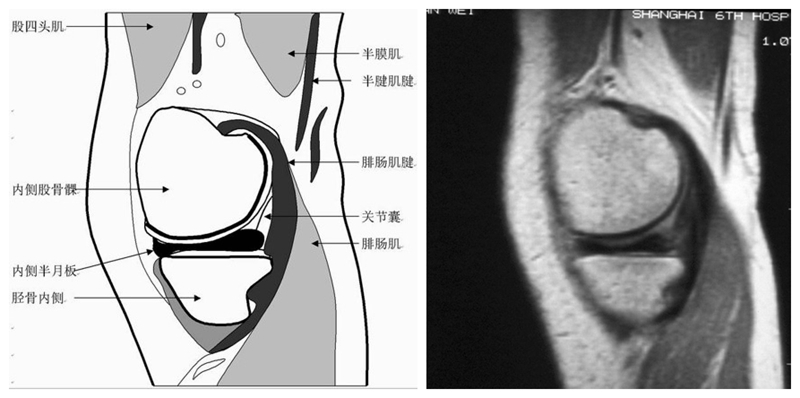

膝关节矢状面正常解剖MRI表现

可整段显像髌韧带、前后交叉、外侧韧副带结构,侧重的股胫软骨中部和半月板前后角,通常是诊断半月板撕裂或变性最为关键的断面。

矢状位解剖第一层

矢状位解剖第二层